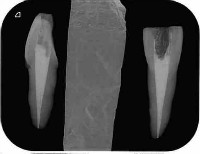

根管の中に入れた最終的なお薬が根の先までしっかり入って、歯の間のコントラストがはっきりしてます。

根管の細菌に感染した歯質をしっかりとって、最終的なお薬で隙間なく埋める事で細菌が感染増殖するのを防ぎます

しっかりと感染歯質をとり、緊密に最終的なお薬をつめているので歯とお薬のコントラストもはっきりしています。